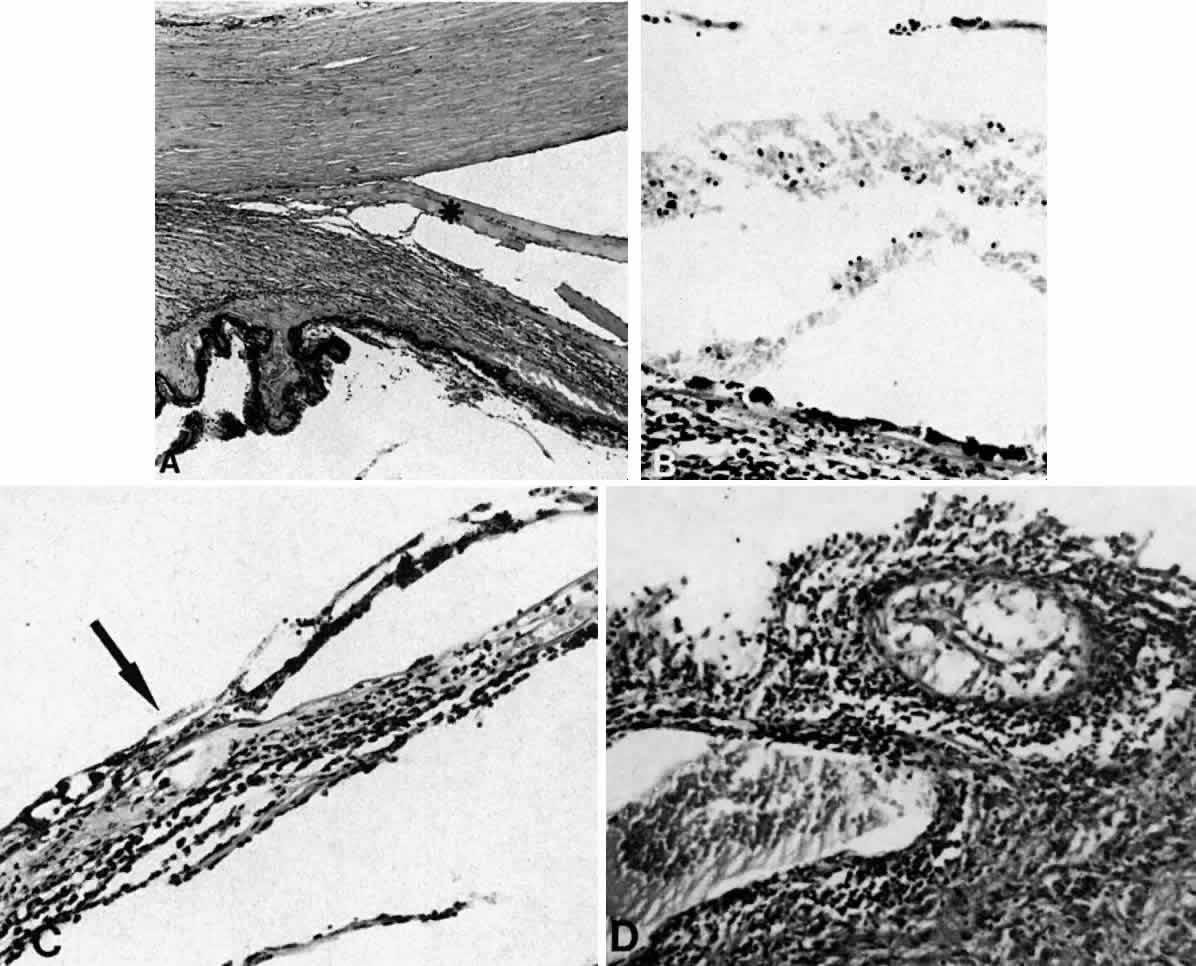

Fig. 8. This choroidal and ciliary body detachment, which occurred after intracapsular cataract extraction, was mistaken for a malignant melanoma.39 A. Iris incarceration in the wound (arrow) and extensive ciliary body effusion consisting of a dense, proteinaceous material (asterisk) (H & E, × 115). B. Effusion of the choroid near the ora serrata by a moderately dense, proteinaceous material without inflammatory cells. Note folds of choroid (arrowheads) (H & E, × 115).

Fig. 9. A. This serosanguineous ciliochoroidal effusion (arrow), which occurred after iridectomy for an iris melanoma in a 68-year-old man, was mistaken for a choroidal melanoma (H & E, × 25). B. Site of the limbal wound (arrowhead) with incarceration of the iris base and residual melanoma in the iris, anterior aspect of the ciliary body, and trabecular meshwork (H & E, × 60).

Fig. 10. A. This extensive ciliochoroidal effusion (asterisk), which occurred 4 years after iridencleisis in a 70-year-old man,39 was mistaken for a malignant melanoma. The iris (arrow) is incarcerated in the limbal wound, and a flat, edematous infiltration bleb (arrowheads) is present (H & E, × 25). B. Area of the ora serrata shows a ciliochoroidal effusion with proteinaceous material separating the tangentially oriented collagen fibers (arrowheads) that connect the choroid and ciliary body to the sclera (H & E, × 115).